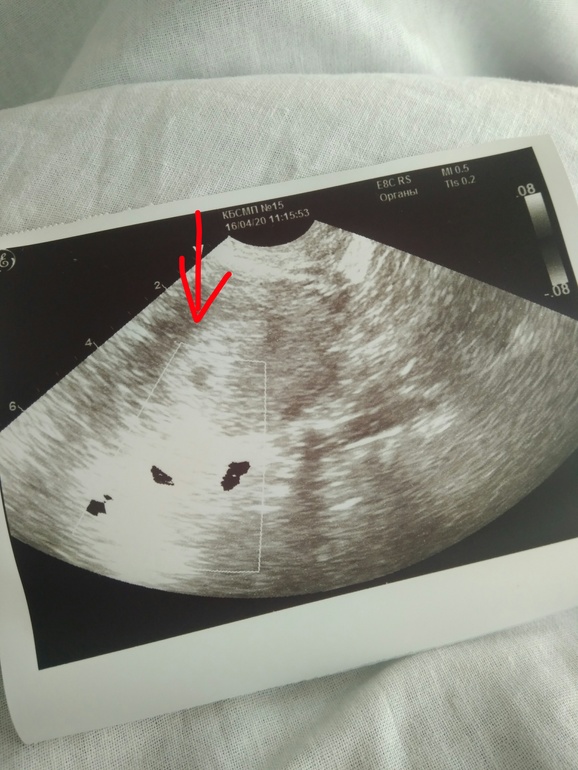

Вчера повторили узи, плодное яйцо уже пропало, осталось только уплотнение эндометрия(( Сегодня хгч 10570, повторят узи и уже назначат таблетки для медикаментозного аборта.

При этом сейчас на узи опять какие-то непонятки.

Оболочка хориона 12 мм, внутри включение жидкости в оболочке 5мм

В самой жидкости ничего не визуализируется😔